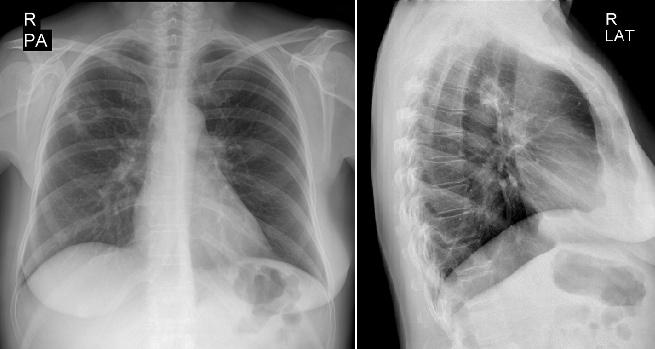

Нормальная рентгенограмма легких: что нужно знать

Раздел: Мудрость в объективе